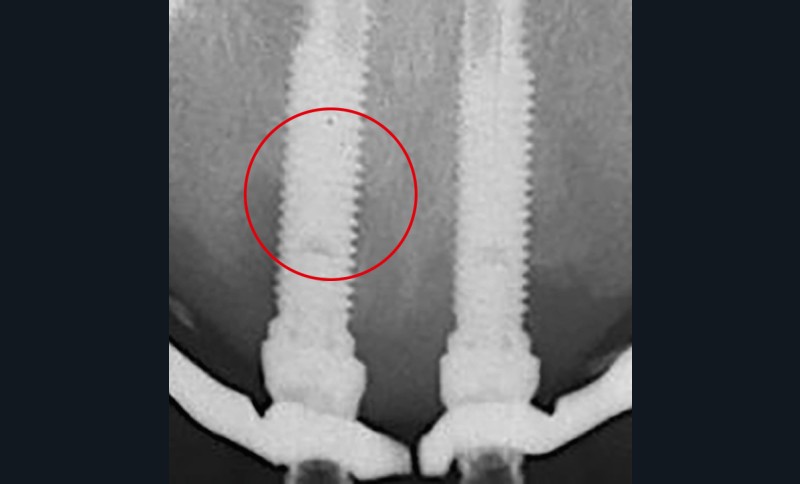

La santé des tissus péri-implantaires

Elle se définit par défaut, se traduit cliniquement par « l’absence d’inflammation, de saignement au sondage, d’œdème et de suppuration », sans tenir compte des profondeurs de sondage [4-6] (fig. 1).